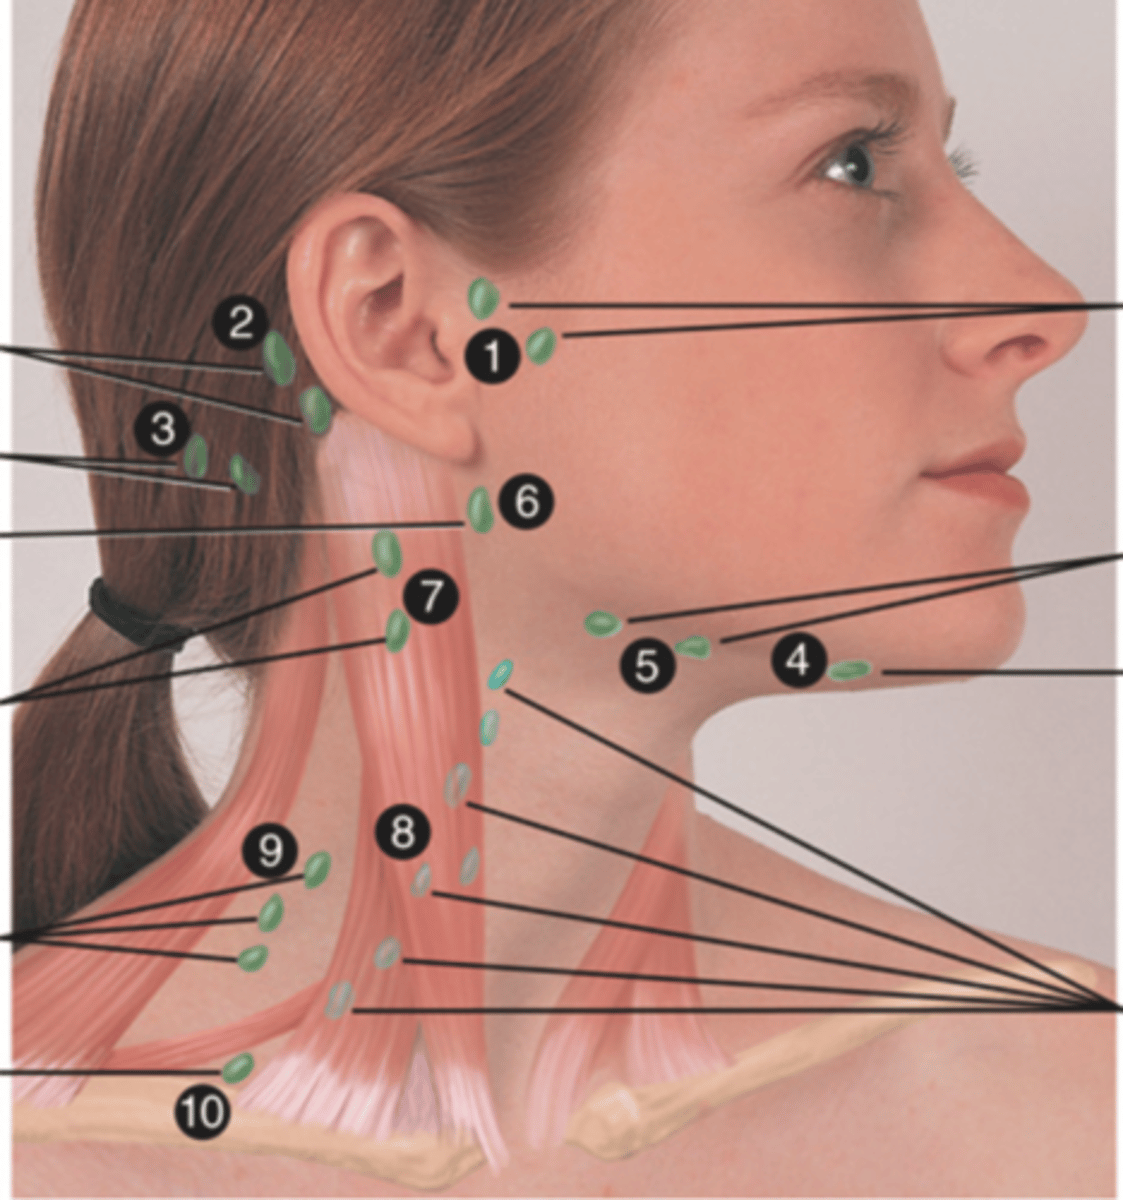

Major Lymph Nodes in the Neck (FUN!)

(Party People Often Sell Sardines Just So Dogs Pee Silver)

Preauricular Lymph Node

Lymph node in front of the ear (1)

Posterior Auricular Lymph Node

Lymph node behind the ear (2)

Occipital Lymph Node

Lymph node at the base of skull (3)

Submental Lymph Node

Lymph node under the chin (4)

Submandibular Lymph Node

Lymph node along base of mandible (5)

Jugulodigastric (Tonsil) Lymph Node

Lymph node under the angle of the mandible (6)

Superficial Cervical Lymph Node

Lymph node overlying the sternomastoid muscle (7); can feel enlarged even when there are no problems

Deep Cervical Chain Lymph Node

Lymph node located on the posterior triangle of the neck (8)

Posterior Cervical Lymph Node

Lymph node in the posterior triangle along the edge of the trapezius muscle (9)

Supraclavicular Lymph Node

Lymph node just above and behind the clavicle, at the sternomastoid muscle (10)